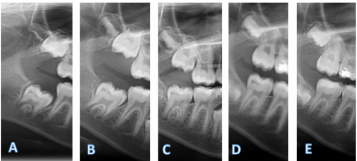

Radiographic examination also showed that the developing lower right permanent second molar exhibited a caries-like radiolucent lesion (Figure 2A). The lesion was located in the distal part of the crown under the DEJ. The diagnosis of pre-eruptive intracoronal radiolucency was confirmed. Since the tooth was unerupted; the patient was asymptomatic; the decision was made to monitor the lesion by periodic panoramic radiographs to follow the progression of the lesion and root development. Consent was obtained from the father for reporting this case. Subsequently the patient was monitored clinically every three months and panoramic radiographs were taken annually. There is no obvious progression of the PEIR size or changes in location noted at age 10 and age 11 years old. (Figure 2BC).

Figure 2. Annual series of panoramic radiographs taken for lesion progression monitoring. A. Baseline radiograph. B. At age 10 years old. C. At age 11 years old. D. At age 12 years old. E. One-year-follow up radiograph postoperatively

At age of 12-year-old, clinically the PEIR-affected tooth had partially erupted; showing darkening of the distal fossa, mesial occlusal discolored groove with no cavitation, nor enamel defects (Figure 3). Radiographic examination revealed two-thirds of the root had developed. The lesion was in the same location, but was slightly larger than in previous radiographs (Figure 2D). Still, tooth was asymptomatic and there were no signs of pulpal involvement. Accordingly, decision was made to seal the tooth and monitor it until complete eruption for final treatment. The tooth was etched using 35% phosphoric acid (Ultra-Etch, Ultradent Products, Inc., South Jordan, UT) then sealed with a resin-based fissure sealant (Concise Light Cure White Sealant, 3M ESPE, St. Paul, MN, USA).

The patient was seen at the 6-month follow-up visit, and was asymptomatic. Clinical examination showed normal response to percussion and cold test. The restoration was intact with no discoloration or signs of marginal leakage. At one-year follow-up, she had the same clinical findings, and radiographic imaging revealed normal periapical area, periodontal ligament space, and bone trabeculation (Figure 2E).